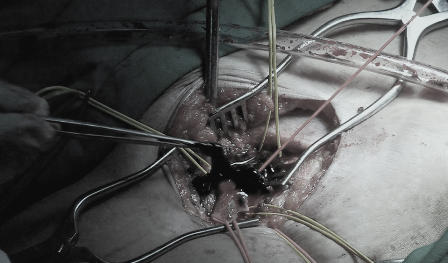

Sau chẩn đoán, bệnh nhân bị tắc tĩnh mạch sâu cấp tính thể nặng, nguy cơ hoại tử chân, có thể dẫn đến đột tử, các bác sĩ khoa Phẫu thuật Mạch máu đã quyết định can thiệp cho người bệnh. Ê kíp bác sĩ đã tiến hành phẫu thuật lấy huyết khối trong lòng tĩnh mạch của bệnh nhân, sau đó nong bóng và đặt stent sửa chữa đoạn tĩnh mạch chậu bị hẹp trên. Hình chụp kiểm tra sau can thiệp cho thấy, lòng tĩnh mạch không còn huyết khối và vị trí tĩnh mạch chậu bị hẹp đã được mở rộng, máu chảy về tim dễ dàng, sức khỏe bệnh nhân nhanh chóng bình phục.

Bằng biện pháp phẫu thuật kết hợp can thiệp nội mạch, bệnh nhân huyết khối tĩnh mạch sâu cấp tính nếu được phát hiện sớm trong vòng 2 tuần có thể được điều trị tốt. Việc can thiệp nội mạch sẽ giúp phẫu thuật thực hiện dễ dàng, đồng thời giúp phát hiện và sửa chữa những thương tổn tắc hẹp của tĩnh mạch bằng cách nong bóng và đặt stent. Kỹ thuật trên lần đầu tiên được thực hiện thành công tại bệnh viện Đại học Y Dược sẽ mở ra phương pháp mới trong điều trị cho bệnh nhân bị huyết khối tĩnh mạch sâu, giúp hạn chế tối đa nguy cơ bệnh tái phát.